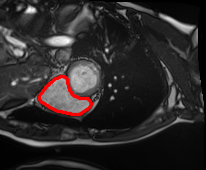

4.4 Comparison with cardic MR images for left ventricle segmentation

In this section, we continue to conduct experiments on cardiac MR images. However, we focus on the right ventricle, which is equally important as the left ventricle in cardiac MR diagnoses. In the near short-axis view, the left ventricle has a crescent shape, while the right ventricle is closer to circular. This does not imply that the right ventricle is easier to segment; in the MR images we use, the right ventricle often shows low-signal-intensity shadows, which may be caused by the imaging characteristics of certain tissues or fluids, leading to interference in segmentation. Moreover, there is a layer of myocardial tissue surrounding the right ventricle that overlaps with the boundary of the right ventricle, posing challenges for accurate identification.

Fig. 8 presents the segmentation results of the right ventricle from the DRLSE-ADMM [WALI2023109105], ABC model [WENG2021115633], RESLS [8765635], the RefLSM, and the ground truth. The results from the DRLSE-ADMM model in the 1st row reveal severe local minima due to low-signal-intensity shadows in the right ventricle. Additionally, both the ABC and RESLS models fail to correctly identify the right ventricle boundary because of the interference from surrounding myocardial tissue, as seen in the 1st and 3rd columns of Fig.8. In comparison, the proposed model gets more satisfactory segmentation results that are closer to the ground truth. Similarly, we evaluate the segmentation performance of all models by calculating the Dice and Precision values and drawing Fig. 9. This overlay plot presents the best, median and worst segmentation results, along with the overall range of outcomes that it is clear that the proposed model segments the right ventricle with greater accuracy than the other models and performs well in different images.